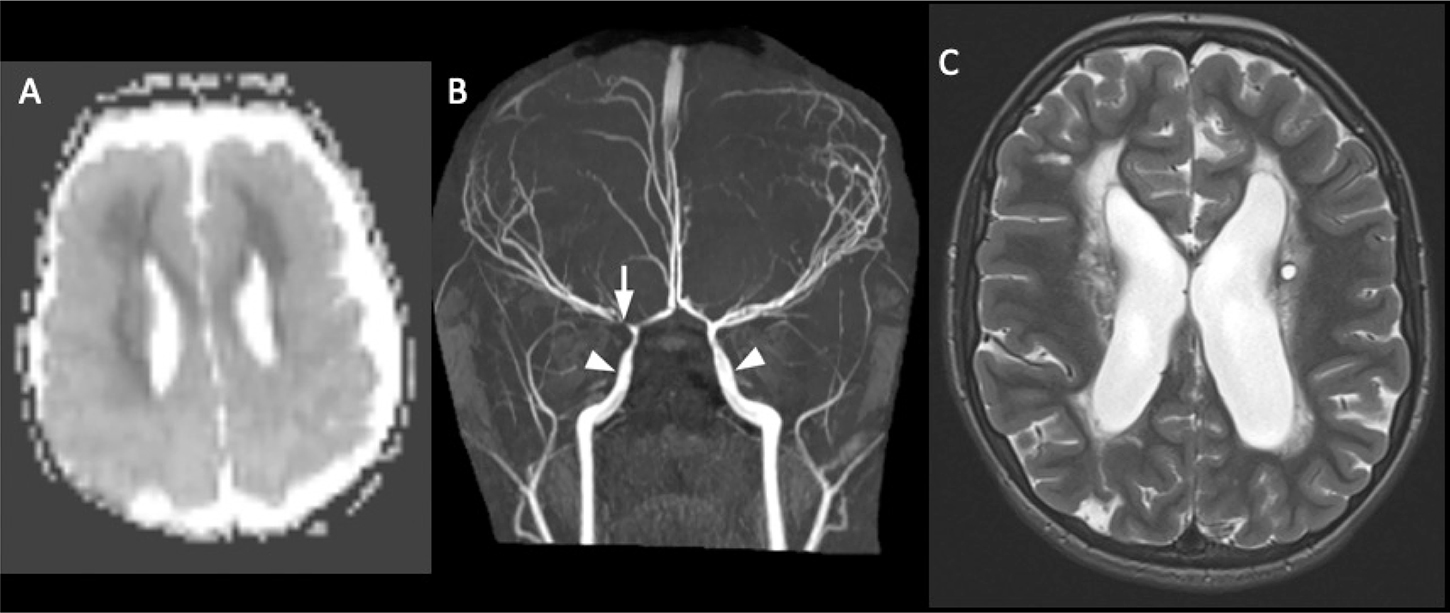

Fig 3

Figure 3. An 11-year-old previously healthy male who presented with left-sided headache, emesis and changing voice. Axial (A) and coronal (B) CT images of the head demonstrate a geographic region of hypoattenuation in the left superior cerebellar hemisphere with loss of grey-white differentiation (circle). C. Axial DWI from MRI the same day demonstrates corresponding reduced diffusion in the left superior cerebellar artery territory (circle). 2D Time-of-Flight MRA of the neck demonstrate irregularity of the right (D) and left (E) vertebral arteries at the junction of the V2 and V3 segments (arrows). Axial CT angiogram (F) confirms irregularity in the vertebral arteries, compatible with bilateral vertebral artery dissection (arrows).